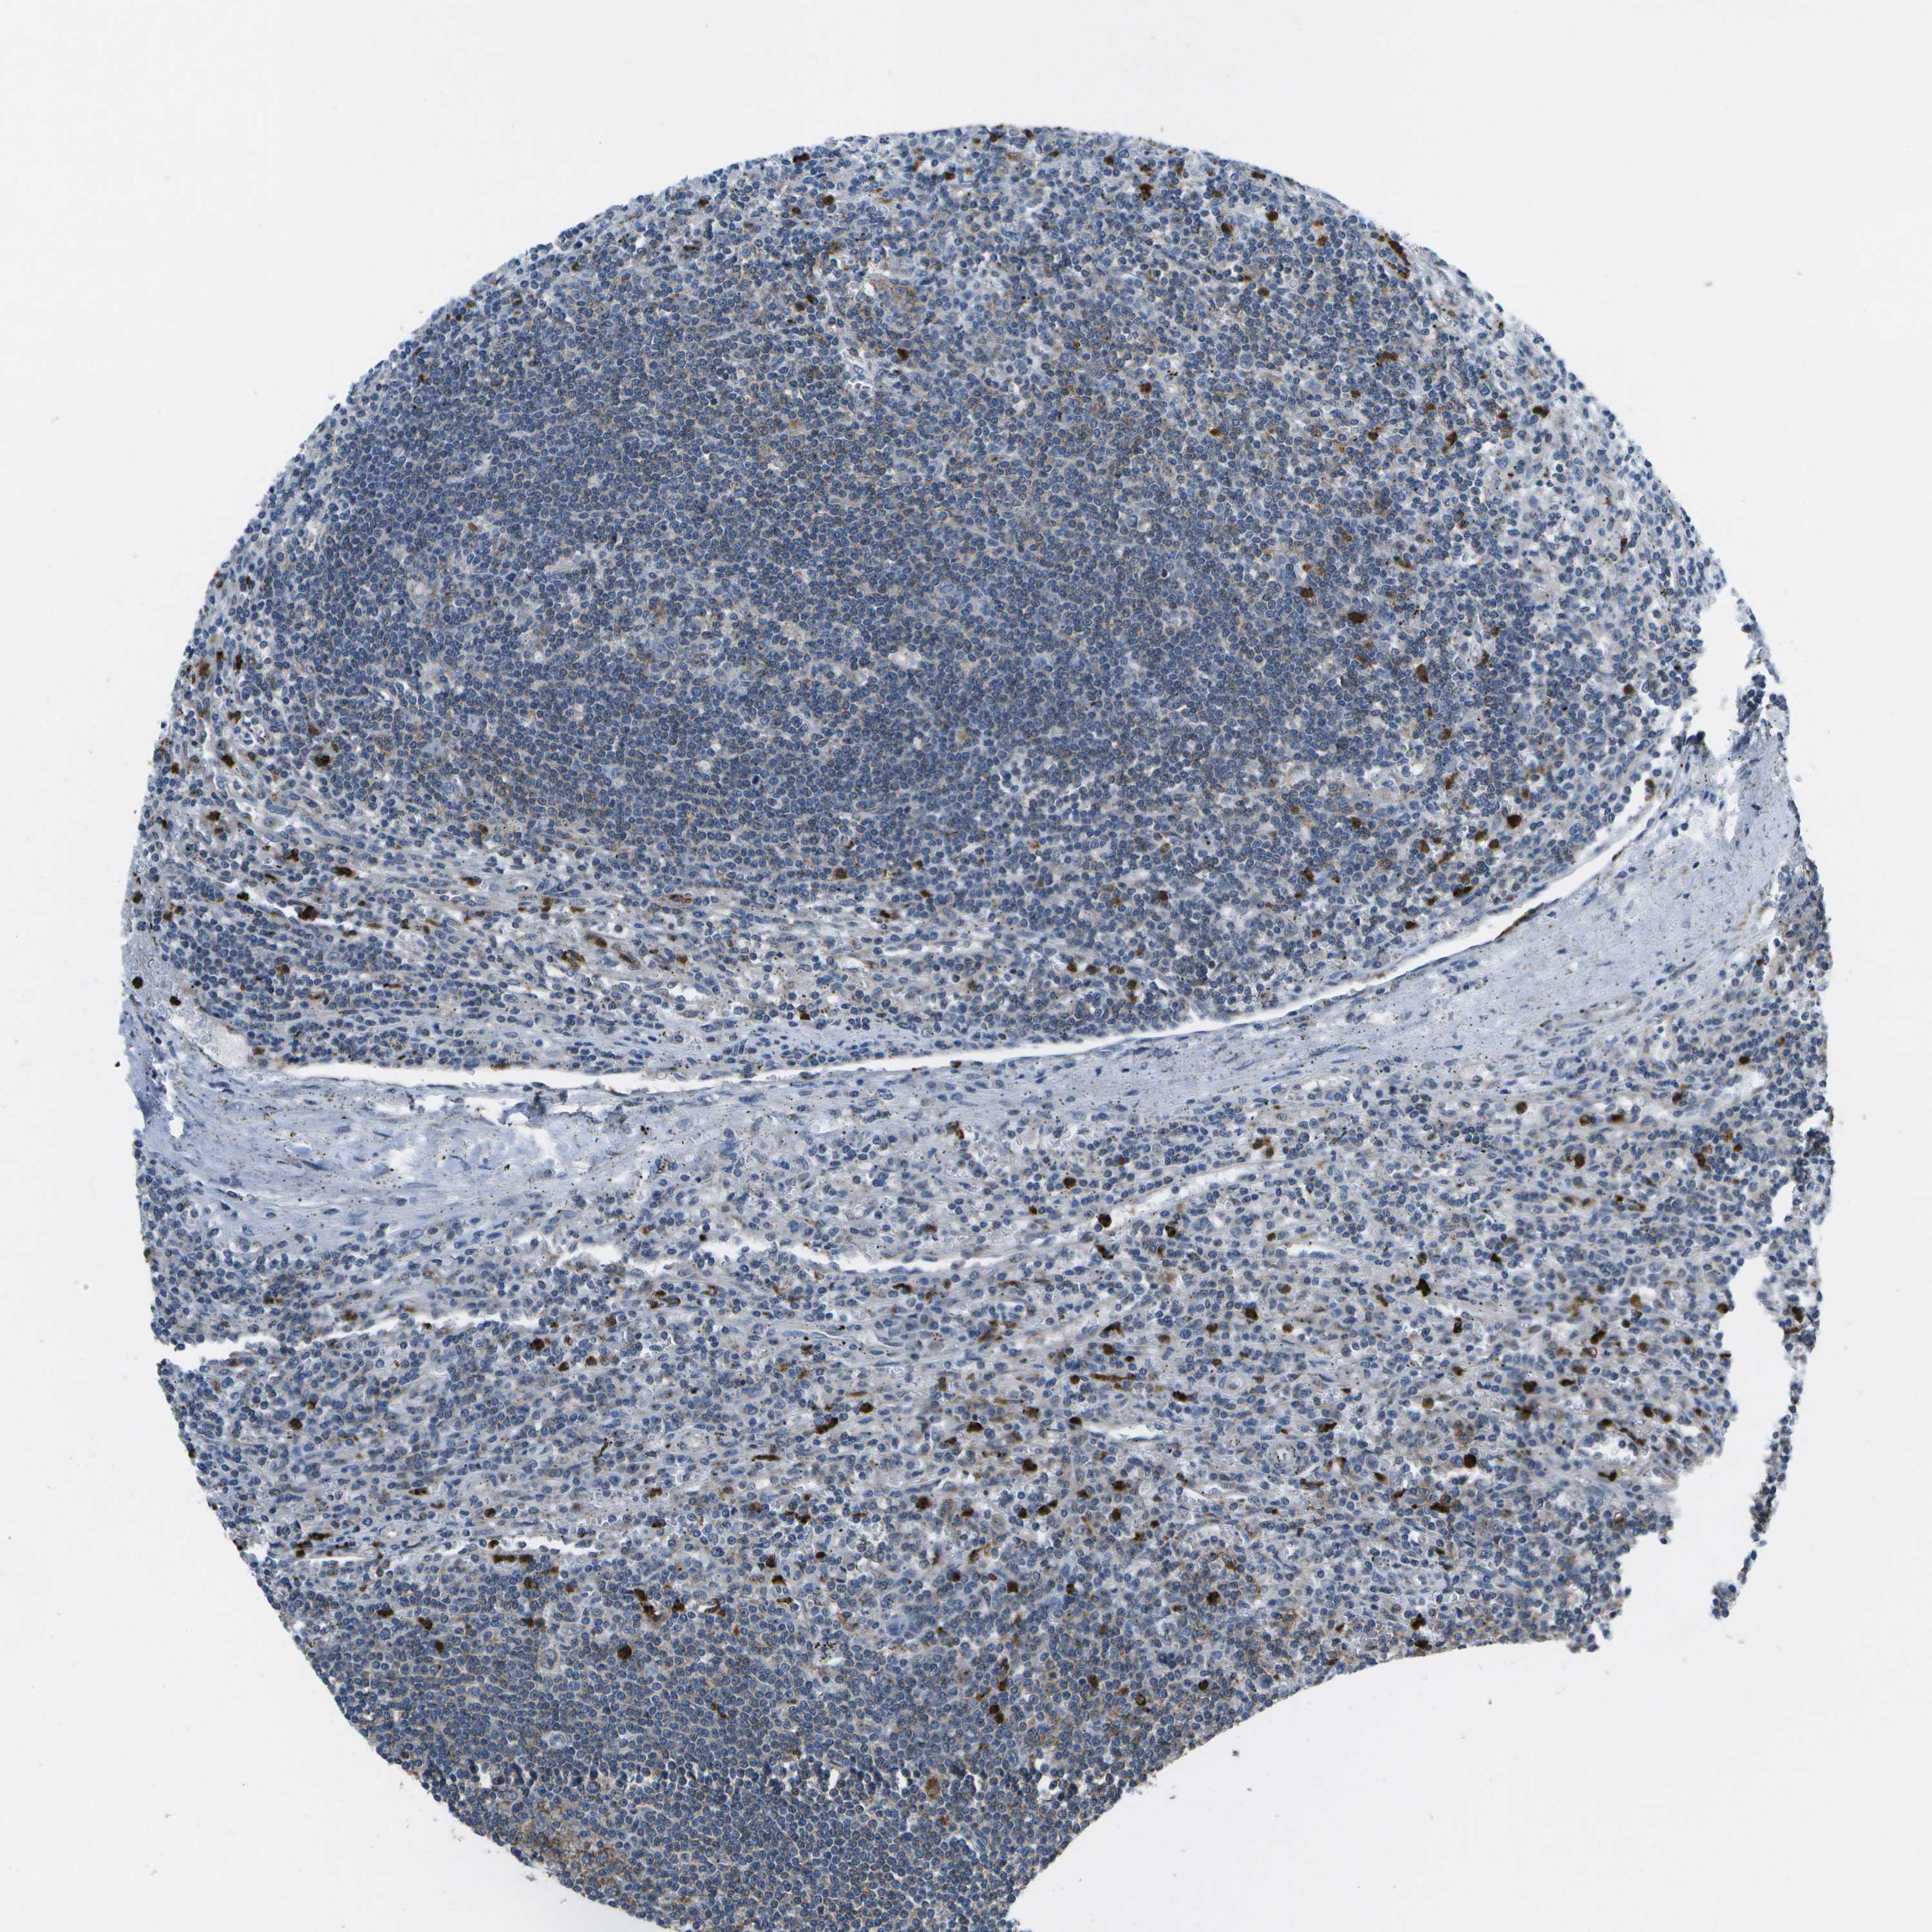

CANCER LYMPHOMA Show tissue menu

LYMPHOMA - Protein expressioni

A mouse-over function shows sample information and annotation data. Click on an image to view it in a full screen mode. Samples can be filtered based on level of antibody staining by selecting one or several of the following categories: high, medium, low and not detected. The assay and annotation is described here.

Each image is clickable and will lead to virtual microscopy that enables deeper exploration of all samples and also displays staining intensity scores, fraction scores and subcellular localization as well as patient and tissue information for each sample.

Antibody HPA017076

Staining

High

Medium

Low

Not detected

Intensity

Strong

Moderate

Weak

Negative

Quantity

>75%

75%-25%

<25%

None

Location

Nuclear

Cytoplasmic/membranous

Cytoplasmic/membranous,nuclear

Hodgkin's disease, NOS

Malignant lymphoma, non-Hodgkin's type, High grade

Malignant lymphoma, non-Hodgkin's type, Low grade